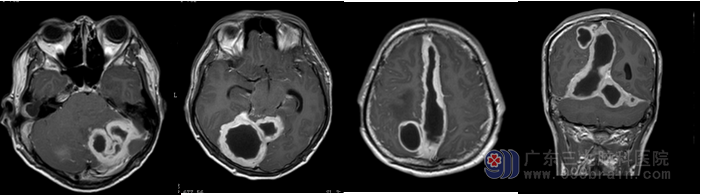

入院后查头颅MR提示:1.大脑镰右侧,小脑幕两侧、右侧额部及右枕部幕下多发硬膜外脓肿形成,右侧顶叶多发脑脓肿,考虑来源于右侧中耳乳突炎所致可能;2.右侧大脑镰下疝合并小脑扁桃体下疝形成;3.垂体变薄,考虑与颅内高压有关可能。

排除手术禁忌症后于2016-07-01行双侧脑脓肿钻孔引流术,术后予反复冲洗引流后,脓液最终引清,患者症状明显改善,后续患者转院进一步行右耳胆脂瘤型乳突炎治疗。